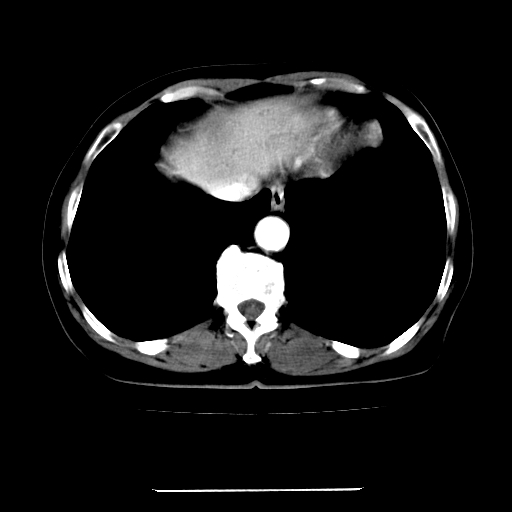

标题: CT22301:女,67岁,上腹部疼痛一周伴皮肤黄染,无发热。 [打印本页]

女,67岁,上腹部疼痛一周伴皮肤黄染,无发热。

左叶肝内胆管结石,并远端肝内胆管扩张。

支持肝内胆管结石并肝内胆管扩张。

肝内外胆管结石并肝内胆管扩张。

建议薄层观察,除外肝门部胆管细胞癌

考虑肝胆管癌;胰头占位?【形态失常,体积增大】

考虑肝门胆管癌伴门脉左支受侵包埋,建议mrcp进一步检查。